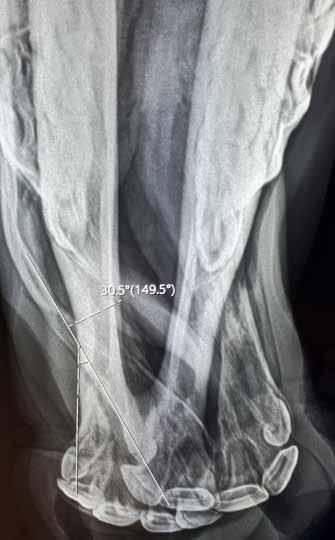

A Rocky Mountain Horse yearling suffering from wry nose presented to the Equine Surgery, Lameness, and Rehabilitation Service at the University of Tennessee, College of Veterinary Medicine in March 2022. The airflow of the yearling was restricted through the nasal cavity, with the right nasal passage especially affected. The premaxillary incisors failed to contact the mandibular incisors because the premaxillae, maxillae, nasal and vomer bones, and the nasal septum deviated to the left of the sagittal plane of the head. The deviation was determined radiographically to be about 30 degrees.

Preoperative imaging.